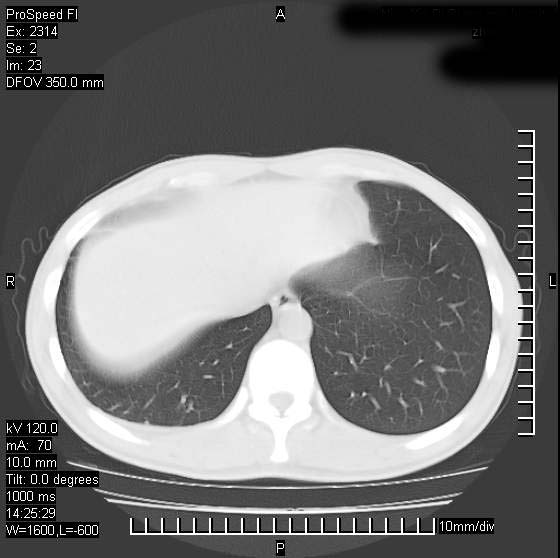

男性,再生障碍性贫血,入院前发热10天,最高40c,右侧胸痛,外院ct示右上,中肺边缘模糊的球性影(就是我现在图中标示的范围),考虑炎症,在我院使用头孢呋辛,洛美沙星10天,高烧消退,自感下午稍有发热,但今天ct示右上,中肺病灶明显扩大,还是考虑炎症,看其中的球型影是否霉菌感染??,是否能排除结核?

肺脓肿,伴双肺播散

支持右肺上叶、中叶外侧段节段性肺炎伴脓肿形成。